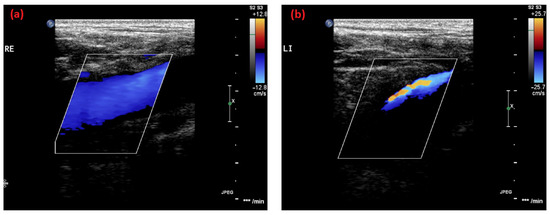

2.1. Case 1

2.2. Case 2

2.3. Case 3